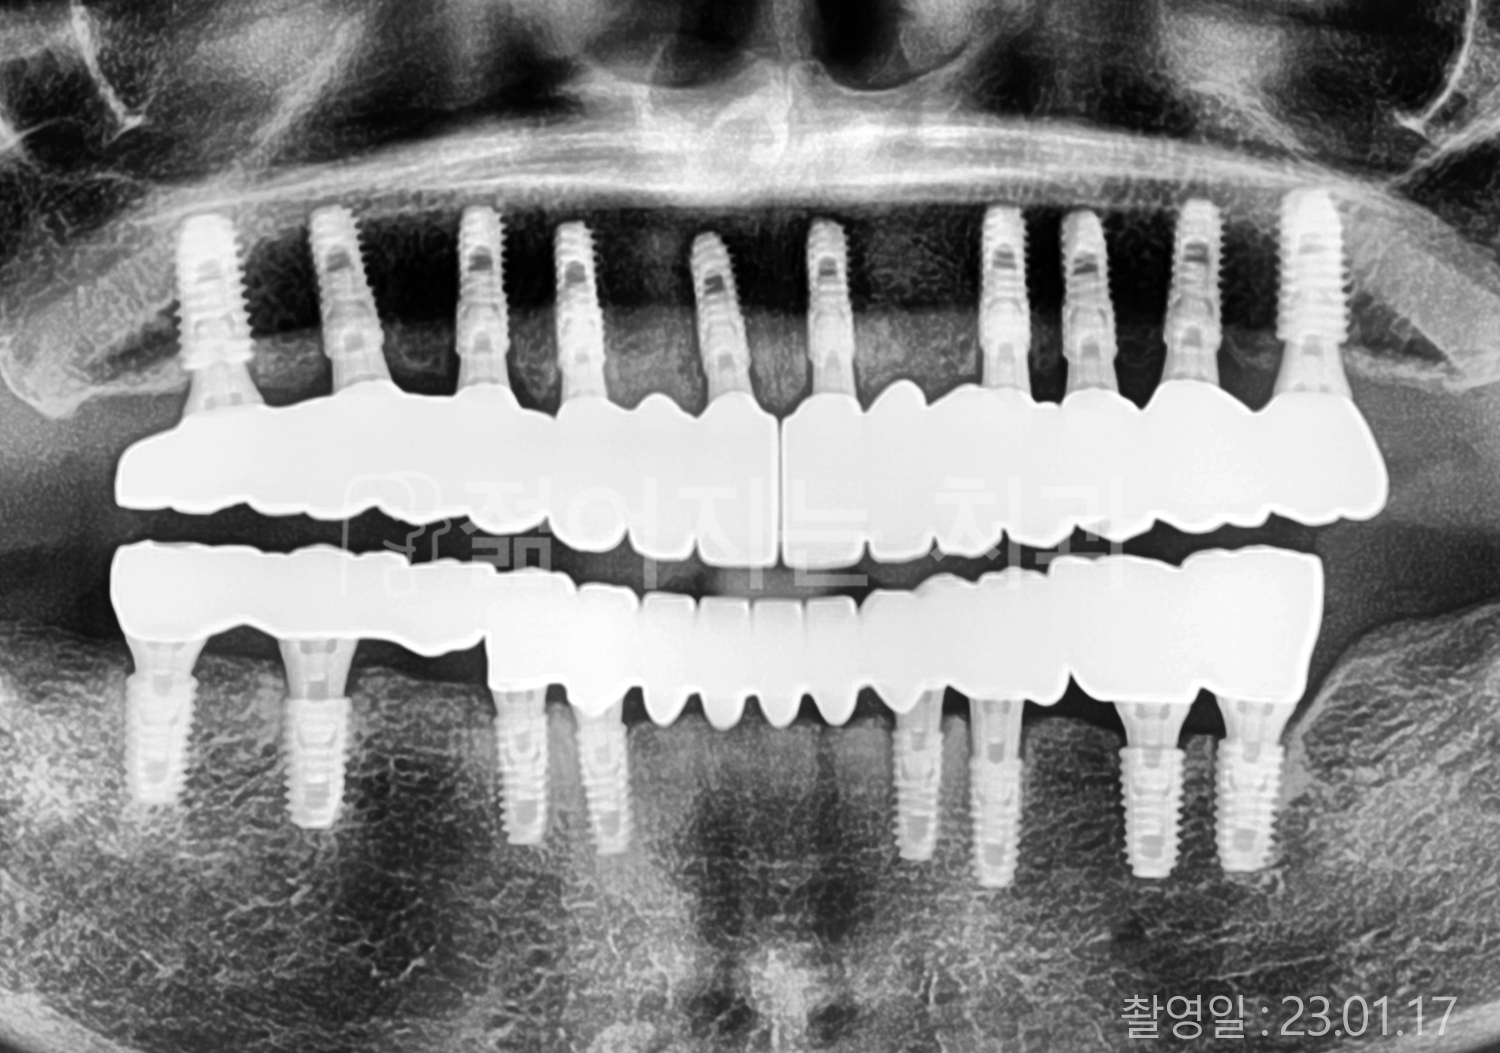

치료부위

식립개수

특이사항

• 60대 전체치아 10개 이상 임플란트